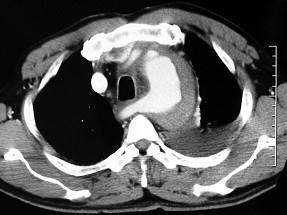

问题 男,58岁,有高血压病史,突发胸背剧痛,CT扫描如图,其最可能的诊断为 ( )

选项 A、高安氏病 B、主动脉夹层动脉瘤 C、主动脉假性动脉瘤 D、主动脉窦瘤破裂 E、主动脉瘤

答案 B